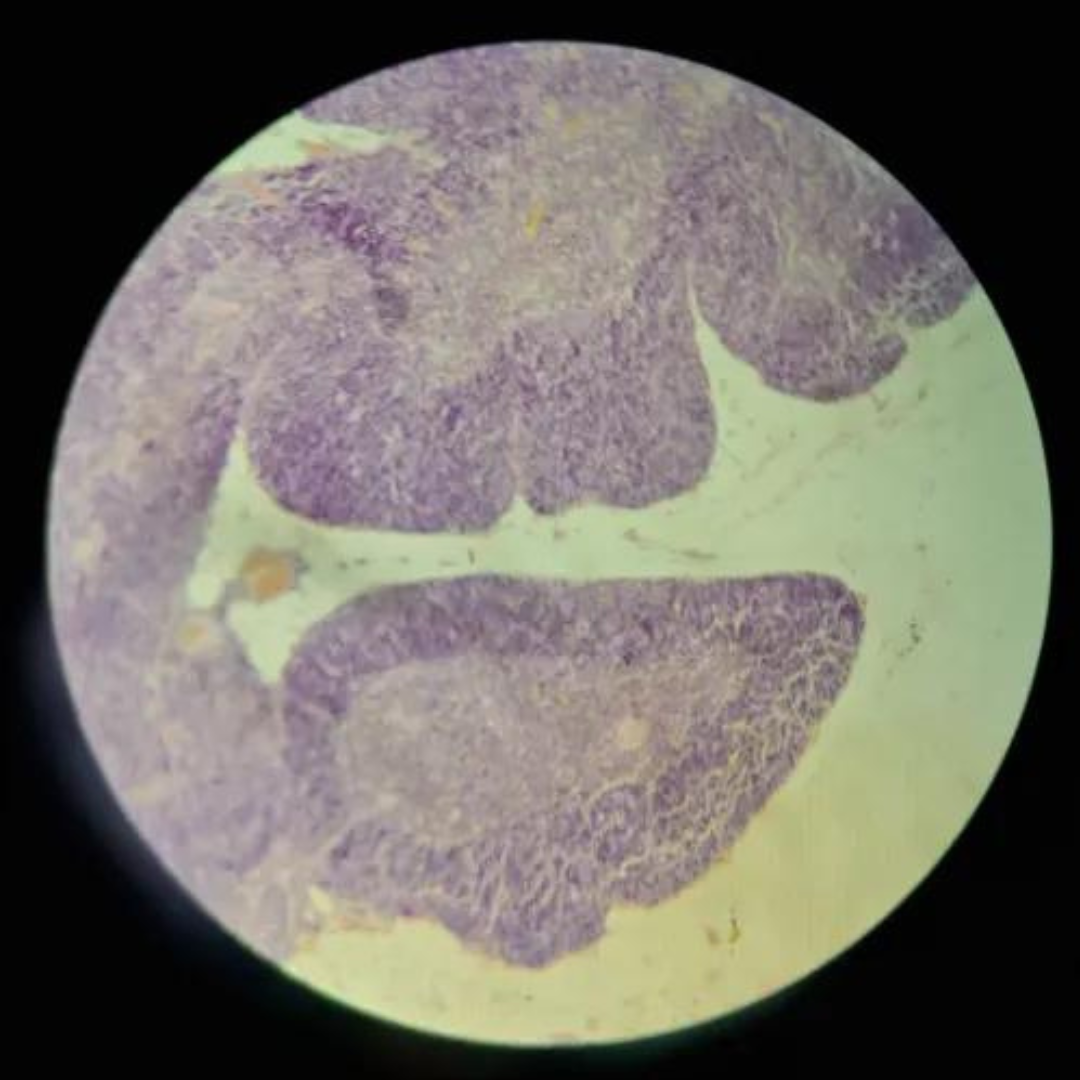

New cards

Thymus (Involuted)

30

New cards

Thymus (Involuted)

31

New cards

Thymus (Involuted)

32

New cards

Thymus

33

New cards

Thymus

34

New cards

Thymus

35

New cards

Thymus (Involuted)